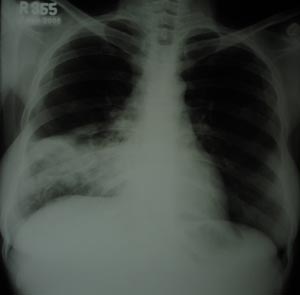

Right lower zone reveals inhomogenous opacity, with right costophrenic angle sparing, suggestive of consolidation. Silhoutte sign present.